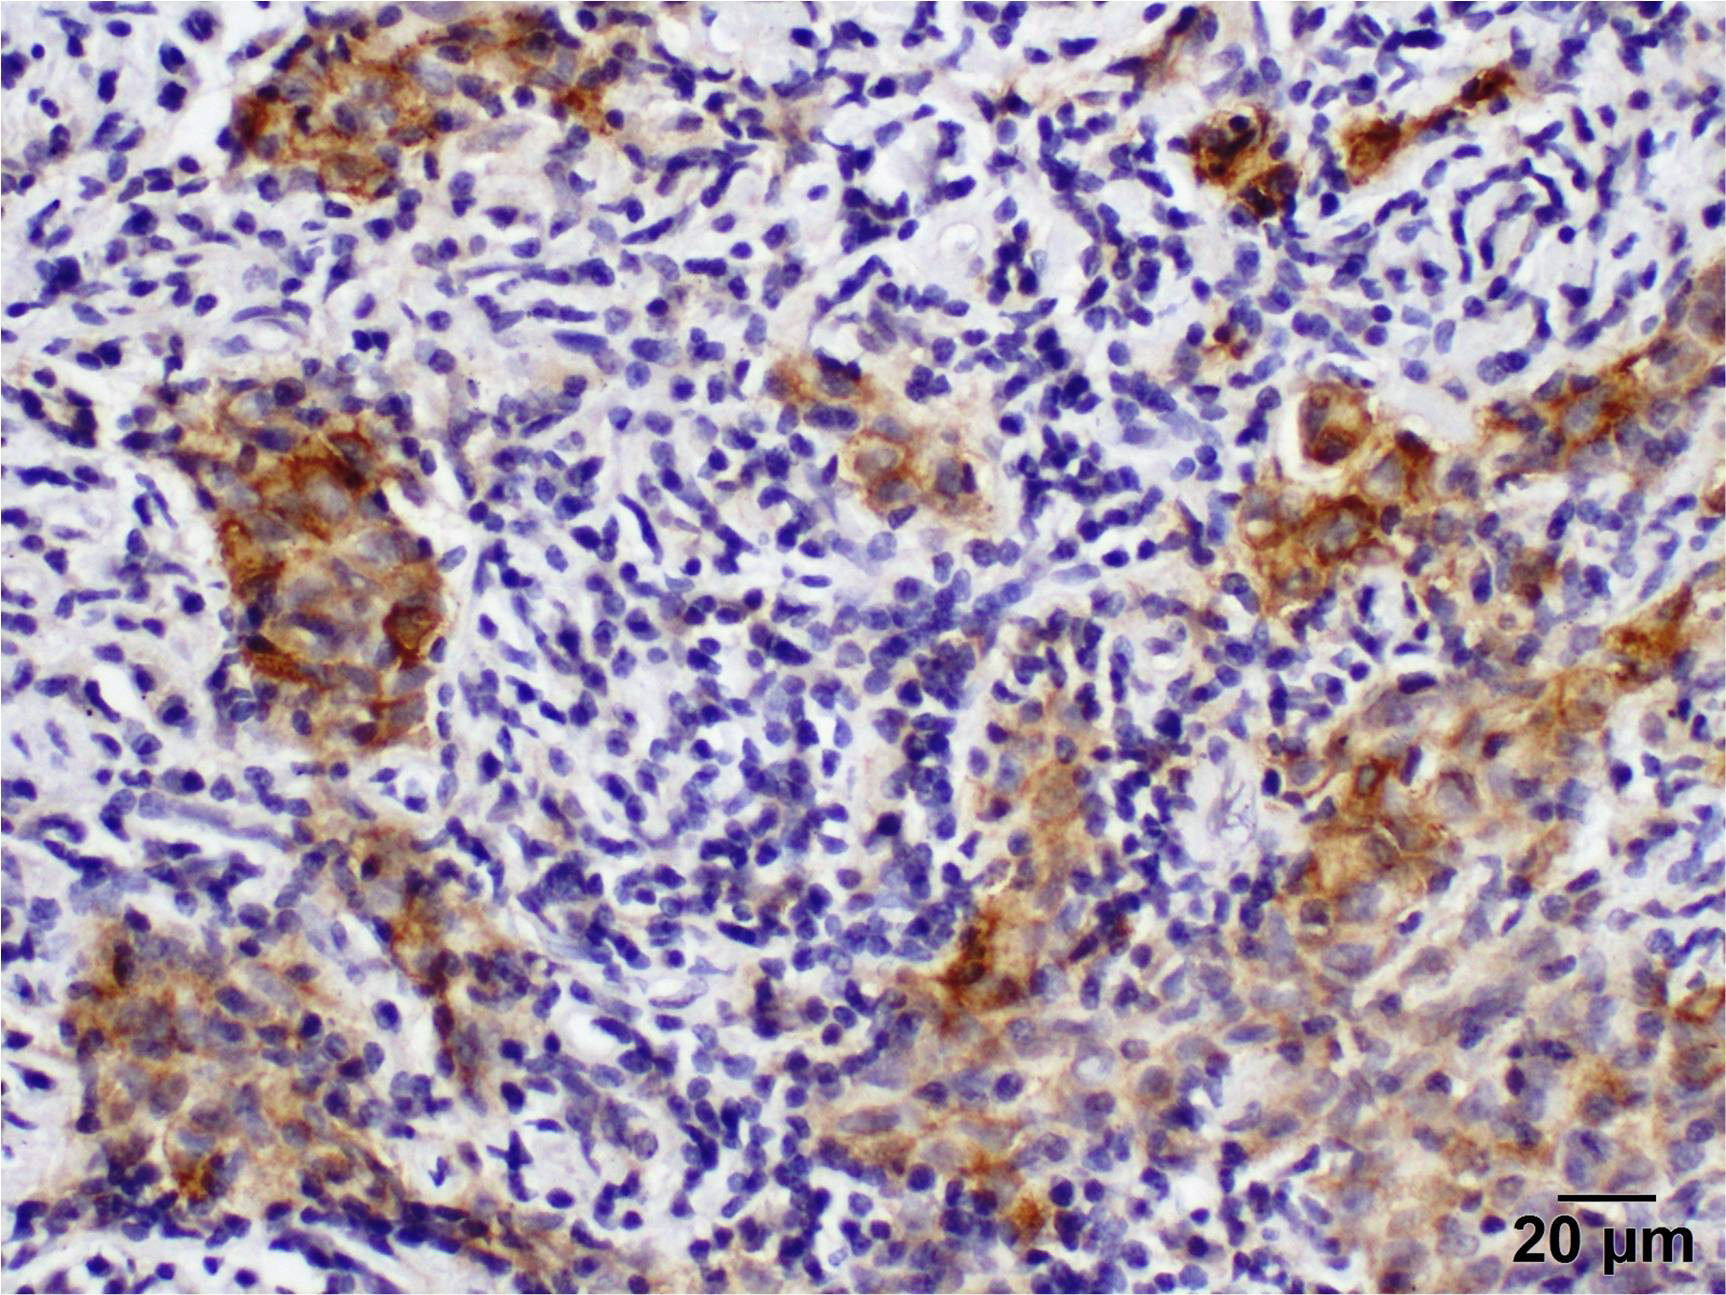

2.4. Immunohistochemistry

2.5. To Evaluate the Level of PD-L1 Expression in the Stroma, the Percentage of Positively